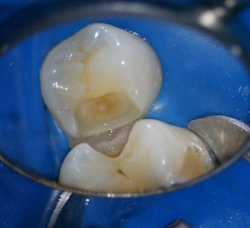

Пример лечения зуба со скрытой кариозной полостью(неосложненная форма).

После удаления эмали размер кариозного процесс становиться более очевидным.

Также зачастую кариозный процесс на контактной поверхности затрагивает оба зуба(на фото справа), как и в данном случае, но за счет ранней диагностики удалось вовремя предотвратить развитие осложнений и ограничиться лишь постановкой пломб.